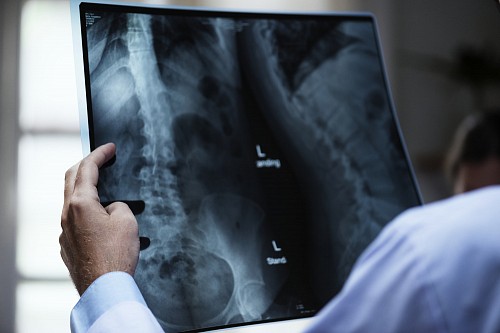

Erfahren Sie mehr +Minimal-invasive Chirurgie ist eine Operation, die darauf abzielt, den Bereich der Interferenz im Körper und den Grad des Gewebetraumas zu minimieren. Die wichtigsten Techniken für minimal-invasive Eingriffe sind die laparoskopische (endoskopische) Chirurgie und die Endoskopie.

Vorteile minimalinvasiver Operationen: extrem geringe Schädigungen des Körpers, ohne die Effektivität des chirurgischen Eingriffs zu reduzieren, der durch den Einsatz von ultradünnem Nahtmaterial und endoskopischer Ausrüstung erreicht wird; es besteht keine Notwendigkeit für eine verlängerte Bettruhe, da die Operationen unter den Bedingungen einer Klinik desselben Tages durchgeführt werden; gut verträglich für Patienten, da kein ausgeprägtes Schmerzsyndrom vorliegt; Durch die Verkürzung der Operationsdauer und die Verringerung der Traumatisierung von Weichteilen wird ein hohes therapeutisches und kosmetisches Ergebnis erzielt.

Es werden spezielle medizinische Geräte wie Glasfaserkabel, Miniatur-Videokameras und spezielle chirurgische Instrumente verwendet, die durch kleine Löcher manipuliert werden. Bilder von inneren Organen werden auf einen externen Videomonitor übertragen und der Chirurg kann auf der Basis des Bildes diagnostizieren und die notwendige Operation durchführen.